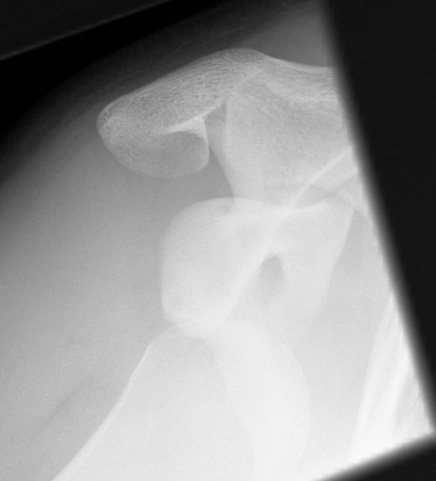

Xray

True AP

Scapular Lateral

Axillary Lateral

Garth (aim beam caudally)

Bony bankart / glenoid rim fractures

Acute bony bankart / glenoid rim fractures

- ? acute repair to reduce instabilty

- ? avoid Latarjet procedure later